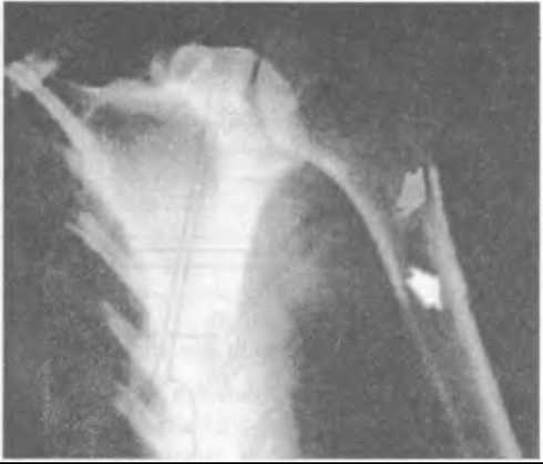

Мал. 403. Періостальна остеосаркома дистальної ділянки стегнової кістки (рентгенограма у двох проекціях).

Мал. 404. Періостальна остеосаркома плечової кістки рентгенологічно.